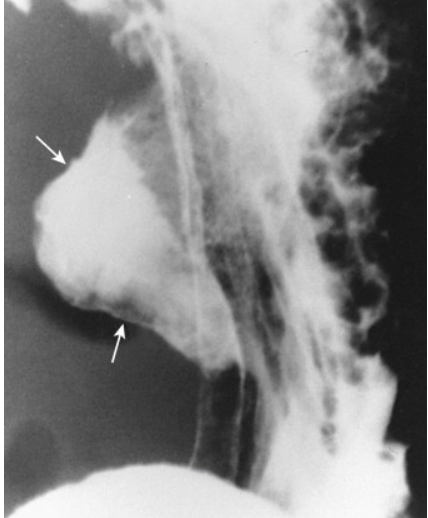

This is a double contrast examination. What is it showing?

A peptic ulcer that is on the posterior wall of the antrum

What does this image show?

Giant gastric ulcer that is located more proximally in the stomach